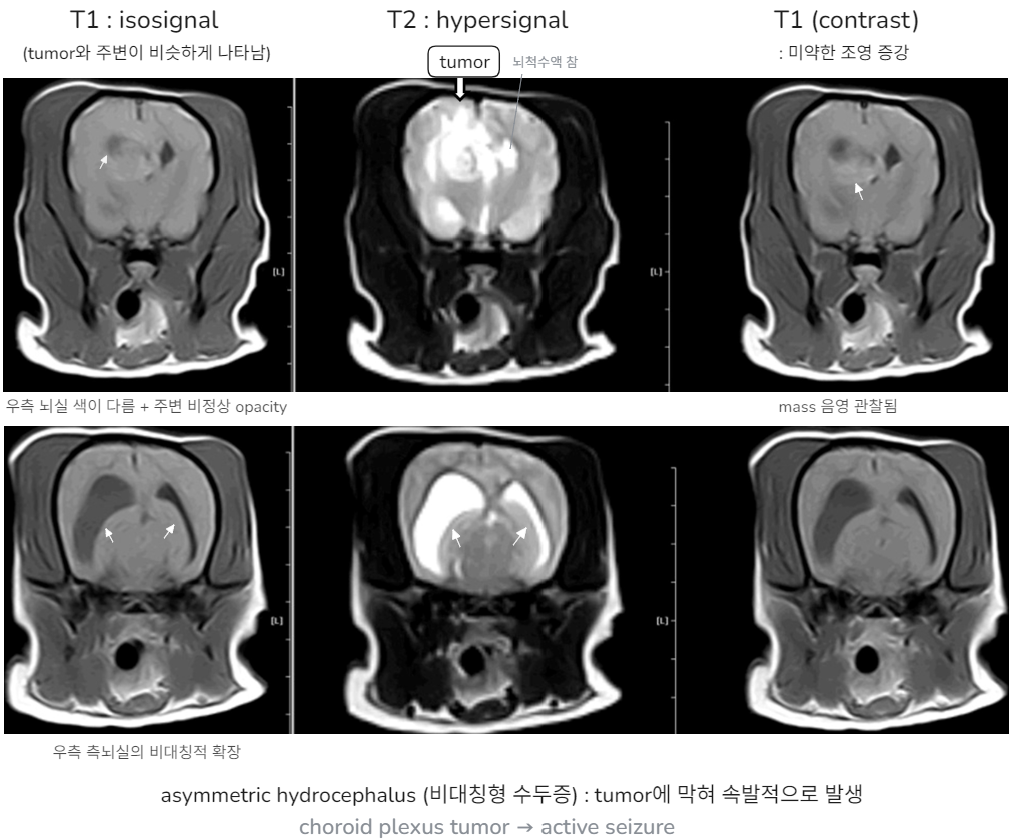

๐ Case 1 : Acquired hydrocephalus (secondary to intracranilal tumor)

A & P

โ Intracranial tumor์ ์ํ aquired hydrocephalus (ํ๊ด ์ ์ ๋ฐ ์ถํ โ CSF ํ๋ฆ์ด ๋งํ hydrocephalus ๋ฐ์) โ TDx) Choroid plexus tumor (carcinoma, papilloma) / DDx) Ependymoma โ ์กฐ์ง ๊ฒ์ฌ๋ฅผ ํตํด ๊ฐ๋ณ (but ํ์ค์ ์ผ๋ก ๋ถ๊ฒํด์ผ ๊ฐ๋ฅ)